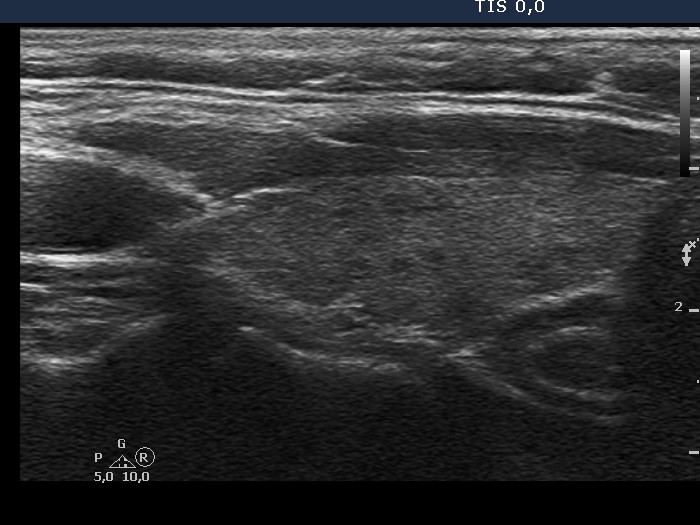

Chronic lymphocytic thyroiditis - Case 29. (ultrasonographic picture 5)

Left lobe, longitudinal view.